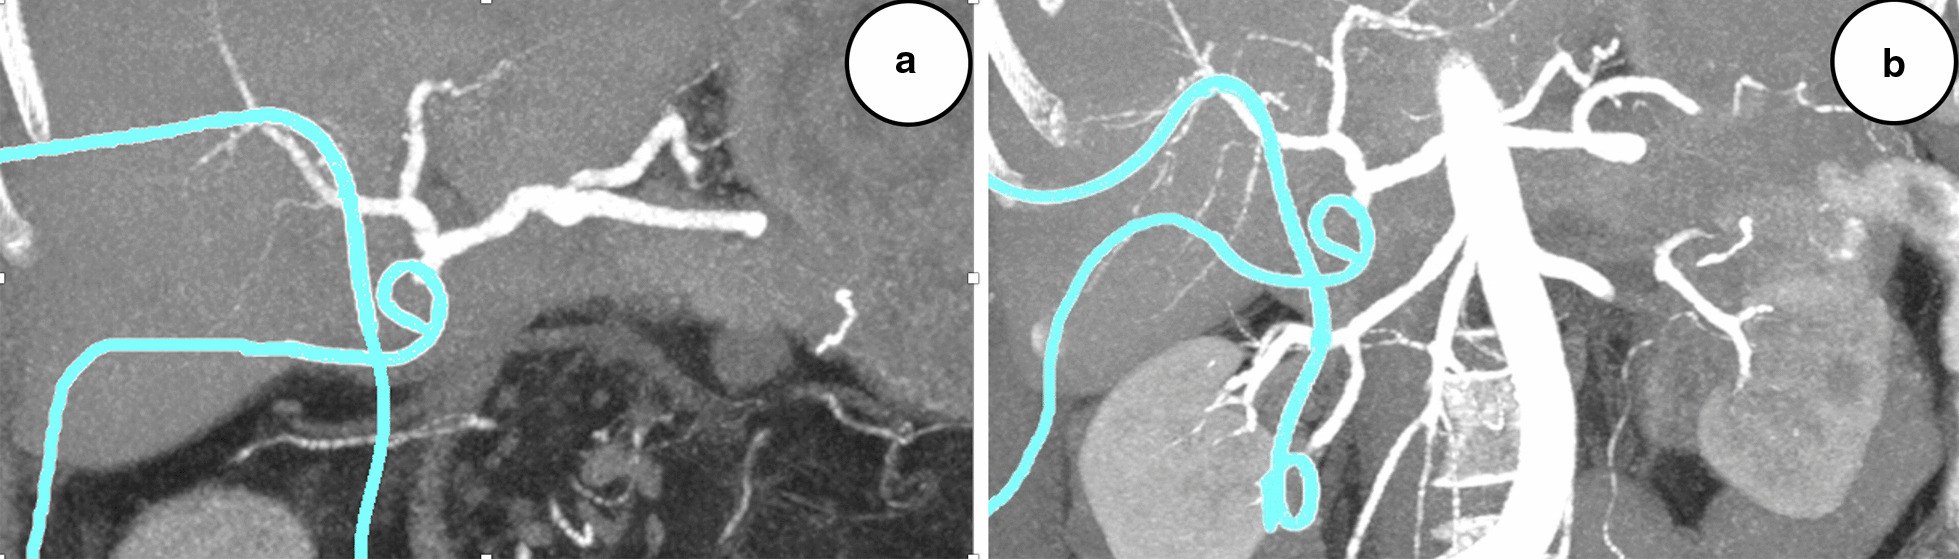

On POD 26, the patient presented blood in both drains and bloody stools. Endoscopy of the gastrojejunostomy (the hepaticojejunostomy could not be visualized because the reconstruction was made on a long Roux loop) and a CT angiography (Fig. 2a) could not localize any evidence of bleeding. The patient was hemodynamically stable, and there was only discrete evidence of bleeding on the hemoglobin curve, presently 89 g/L (98 g/L on the day before and had been stable at approximately 100 g/L without transfusions during the entire preceding postoperative period). Two units of erythrocytes were administered, and on the next day the hemoglobin level was 107 g/L. On POD 28, the patient had a new episode of bleeding in both drains and multiple bloody stools. A repeat endoscopy and CT angiography (Fig. 2b) were both unremarkable. Besides discrete pallor and tiredness, the patient was still in good clinical condition with stable vitals; hemoglobin level was 86 g/L, and after one erythrocyte transfusion it was 93 g/L. Because of continuous bleeding but no identified source, an empiric suspicion of intraabdominal bleeding was raised, and a conventional selective angiography was performed on the next day, revealing a contrast leakage from the gastroduodenal artery (GDA) stump (Fig. 3a), which was coiled successfully (Fig. 3b). The biliary drain had to be changed because it was completely obliterated by blood clots. The clinical conclusion was that of a grade B hemorrhage, and that the blood from the GDA stump had traveled through the insufficient hepaticojejunostomy into the biliary tree and small intestine, causing the presence of blood in both drains and bloody stools (Fig. 4). During the next couple of days, the intraabdominal drain was removed, and the patient was discharged with the biliary drain in situ on POD 45. Her hemoglobin level was 93 g/L, and inflammatory parameters and liver function tests were unremarkable.

Fig. 2.

a Computed tomography angiography, coronal section of the upper abdomen, postoperative day 26, showing the celiac trunk and all main branches (splenic, left gastric, and common hepatic arteries), as well as the gastroduodenal artery stump, the proper hepatic, right hepatic, and left hepatic arteries, with no evidence of bleeding. Pigtail drains can be seen in turquoise. b Repeat computed tomography angiography of the upper abdomen performed on day 28, also without evidence of bleeding from any of the above-mentioned vessels. Pigtail drains can be seen in turquoise